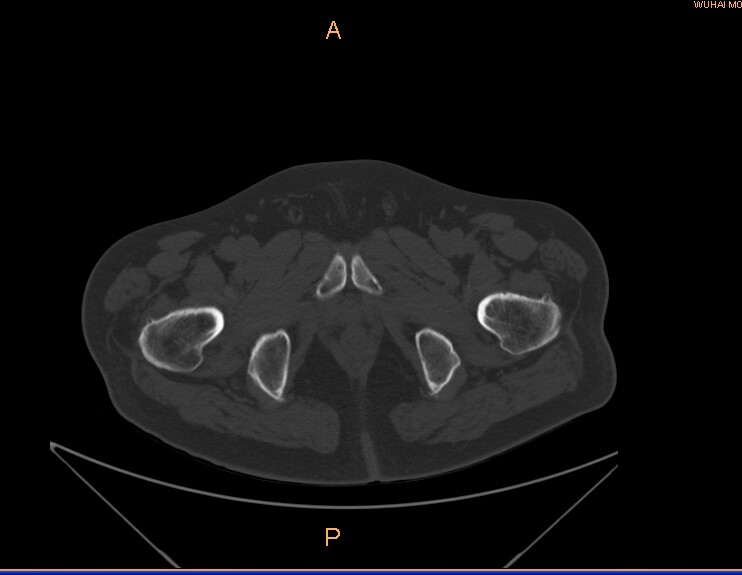

标题: CT29088:左股骨颈 [打印本页]

左侧股骨颈疼痛。

左股骨颈软骨瘤可能,建议增强或mri

内生软骨瘤。

不排除骨样骨瘤

不排除左侧股骨颈内生软骨瘤可能。

内生软骨瘤年龄较小,分叶状,局部皮质有改变,钙化为环形半环形,没有这么粗大。

左股骨颈软骨瘤可能,建议增强或mri  。